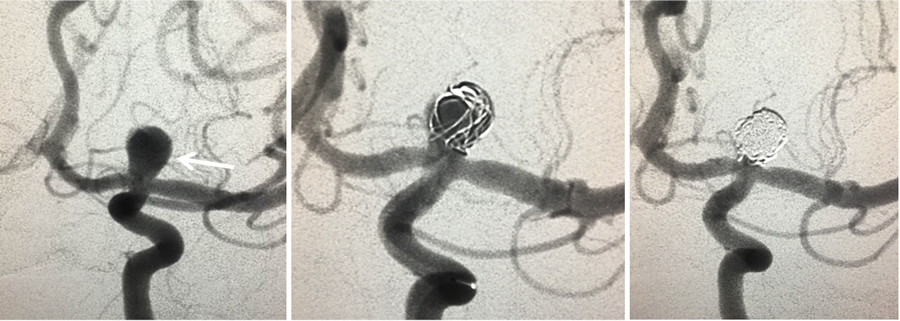

Endovascular coiling is the process by which an aneurysm is blocked with coils to stop blood flow. This is a minimally invasive procedure, meaning that instead of cutting into the skull to treat aneurysms in the brain, it’s done by inserting catheters up through arteries until it reaches the damaged area where platinum coils are released to coagulate (embolization) the aneurysm and prevent blood from entering it.

Figure 3. Anterior 2D angiographic view of a cerebral aneurysm (white arrow) located at the left carotid artery bifurcation (left). The cerebral aneurysm after one coil has been placed inside the aneurysm (middle) and the final image (right) after the coiling has been completed demonstrating aneurysm occlusion.